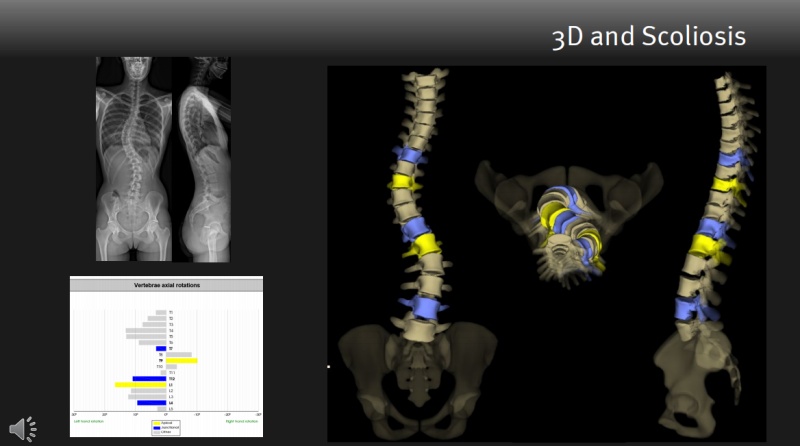

脊柱侧弯是脊柱的非正常弯曲。典型的脊柱侧弯包括三维的脊柱和肋骨畸形。根据度数的变化,脊柱从侧面弯曲,有时椎骨有轻微旋转,导致髋部或肩部出现不平衡。

是目前世界上唯一能在受检者负重位(站姿或坐姿)情况下进行全身三维扫描的超低放射剂量的X射线扫描系统。

EOS具有绿色、高效、精准、智能四大优势

EOS总检查时间为4分钟,包括正侧位扫描,极大提高了医院的工作效率。可以精准的重现全身骨骼整体三维结构自动计算临床参数,帮助医生理解和评估脊柱在功能位的平衡与代偿状态。让临床医生能够更直观、更准确、更个性化的为患儿制定诊疗计划。